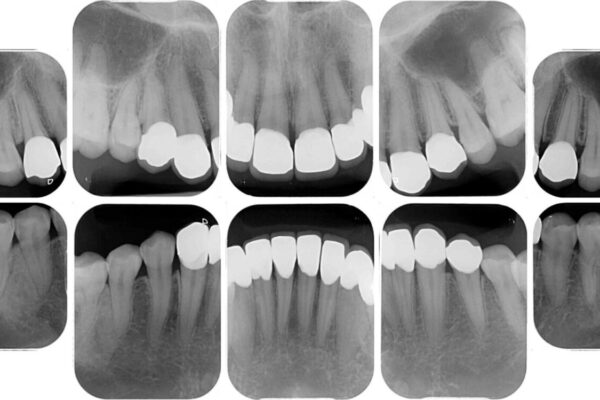

上下前歯や奥歯の虫歯治療を希望して来院された患者様です。

全顎的にむし歯が多く、根管治療の必要な奥歯や、審美的に気になっている前歯を中心にオールセラミッククラウンにて補綴治療を行うこととしました。

治療前

• むし歯だらけの前歯をオールセラミッククラウンできれいに 治療前画像